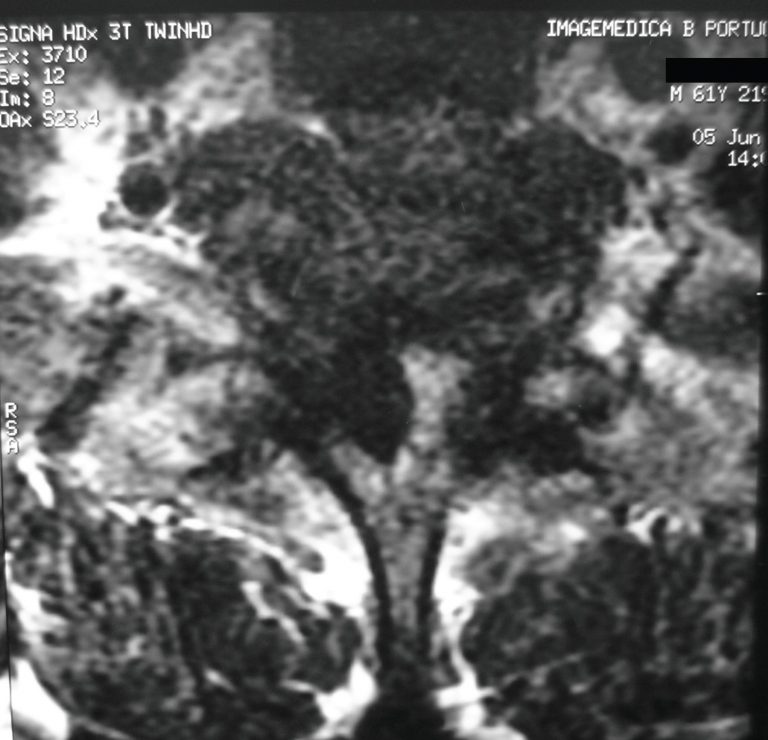

Lumbar synovial cysts are an uncommon cause of back pain and radiculopathy, usually manifesting with gradual onset of symptoms, secondary to involvement of the spinal canal. Rarely, intracyst hemorrhage occurs, and may acutely present as radicular – or even spinal cord – compression syndrome. Synovial cysts are generally associated with degenerative facets, although the pathogenesis has not been entirely established. We report a case of bleeding complication in a synovial cyst at L2-L3, adjacent to the right interfacet joint, causing […]